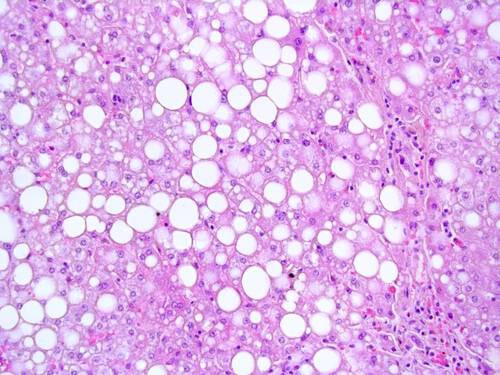

Viele Menschen leiden an einer nicht durch Alkohol verursachten Fettlebererkrankung. Konkrete Zahlen fur Deutschland gibt es bislang nicht. .Die NAFLD stellt eine der haufigsten Lebererkrankungen in den Industrielandern dar. Sie ist unter anderem ein Risikofaktor fur die Entstehung der Leberzirrhose wie auch eines Leberzellkrebses, warnt Bergheim. An der Entstehung einer nicht-alkoholischen Fettlebererkrankung sei vor allem eine Ernährungsweise mit einer übermäßigen Zufuhr an Kohlenhydraten und Fett schuld.

Besonders Menschen mit Adipositas (Body Mass Index (BMI) . 30 kg/m2) sind betroffen, da sie Fett auch im Bauchraum und in Organen wie der Leber einlagern. Bei Menschen mit starkem Ubergewicht und bei Patienten mit Typ-2-Diabetes ist das Risiko, an einer NAFLD zu erkranken, deutlich erhoht. Da eine ubermasige Energiezufuhr nicht selten auch mit Alkoholgenuss einhergeht, ist es jedoch oftmals schwierig, eindeutig zwischen der alkoholischen und nicht-alkoholbedingten Fettleber zu unterscheiden.

Die Forscher im Kompetenznetz Adipositas haben zudem Patienten mit NAFLD sowie eine gesunde Kontrollgruppe (Abbildung 1) untersucht. Wie bei den Mausversuchen fanden sie auch beim Menschen heraus, dass neben TLR4 noch andere dieser TLRs in den Lebern der Patienten mit NAFLD aktiv sind, die sich negativ auf deren Gesundheit auswirken. In weiteren Untersuchungen soll nun erforscht werden, welchen Einfluss die jeweiligen TLRs auf die Entstehung der NAFLD haben. Die Ergebnisse sollen dazu dienen, entsprechende Therapiemaßnahmen entwerfen zu können.